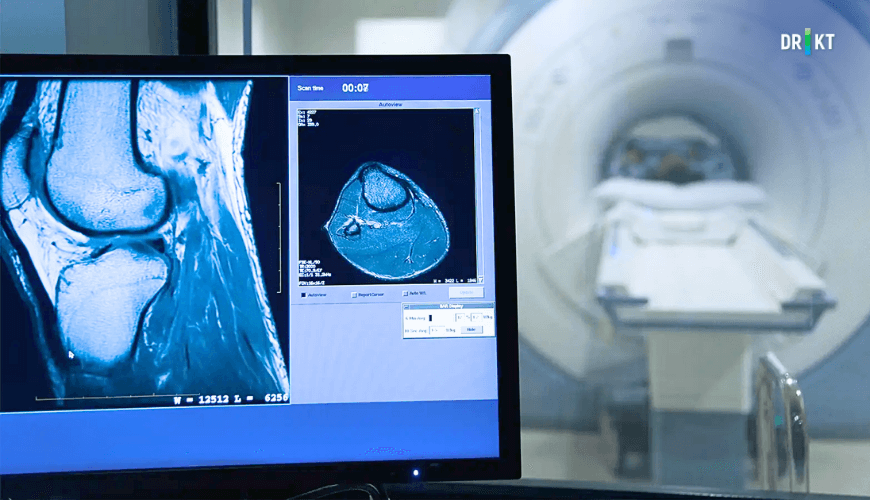

Bir yaralanma, hastalık süreci veya anormal bir durumun mevcut olup olmadığını gösteren görüntüler oluşturmak için hızla değişen manyetik alanlar, radyo dalgaları ve bilgisayar kullanılarak MR taraması gerçekleştirilir (Resim 1).

MR makinesi, bir tüpe benzer ve tarayıcının içine doğru taşınan düz bir yatak bulunur. MR çekimi sırasında bu yatağa uzanırsınız. Vücudunuzun görüntüleme yapılacak kısmına bağlı olarak baş veya ayaklardan başlayarak yatak cihaza doğru taşınır. Manyetik alan ve radyo dalgaları kullanılarak MR çekimi gerçekleştirilir (Resim 2).